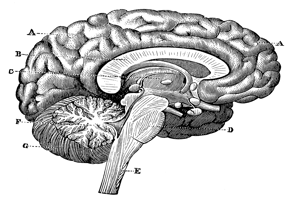

• Neurodiversity